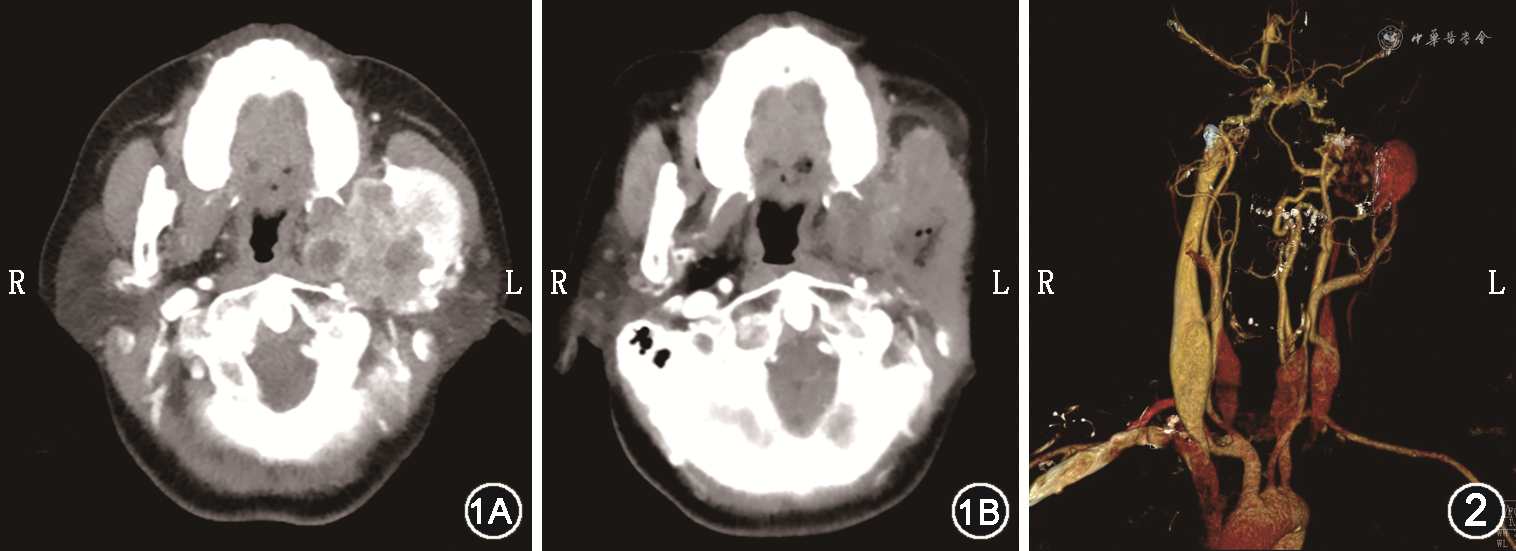

患者女,54岁,因“发现左侧耳前肿物半年”于2021年4月14日就诊于湖南省人民医院耳鼻咽喉头颈外科。半年前肿块大小约2.0 cm×2.0 cm×1.5 cm,患者无不适症状,未予诊治。2021年4月5日患者在当地县人民医院行CT检查示左侧咽旁间隙团块状软组织肿块可疑恶性。4月8日就诊于长沙市某医院,行MRI检查示左侧咽旁间隙肿块恶性可能性大。为求进一步诊治就诊于我院。患者既往无特殊病史。专科查体:左侧耳前可触及一大小约4 cm×4 cm×3 cm肿物,质硬,活动欠佳,边界不清,无明显触痛及压痛,张口无明显受限,舌体活动可。颈软,气管居中,甲状腺不大,未扪及明显结节,无颈静脉充盈,颈部未扪及明显浅表淋巴结。血生化检查无明显异常。影像学检查:全身骨扫描示左侧面颊区代谢异常增高;甲状腺彩超示甲状腺左侧叶低回声结节并钙化甲状腺影像报告和数据系统(TI-RADS)4b类,甲状腺左侧叶低回声结节TI-RADS 4a类,甲状腺双侧叶混和回声结节TI-RADS 3类;腮腺增强CT示左侧咽旁间隙占位伴左侧下颌骨破坏、甲状腺左侧叶病灶(图1);头颈部CT血管成像(CTA)示左侧咽旁间隙肿块由左侧颈外动脉分支供血,引流静脉为颈外静脉(图2)。患者于超声下行甲状腺左侧叶结节及左侧咽旁间隙肿物穿刺活检,病理结果提示甲状腺乳头状癌、左侧咽旁间隙肿物倾向具有血管周上皮样细胞分化的肿瘤。遂于2021年5月6日在全身麻醉下行颈外进路咽旁间隙肿物摘除术+下颌骨部分切除术+面神经松解减压术+甲状腺全切术+左侧Ⅵ区淋巴清扫术。针对咽旁间隙肿物,于左侧耳部做S形切口,术中见质硬肿物位于腮腺深叶深面,侵犯左侧下颌骨升支达髁状突,保护好面神经,从左侧下颌角处截断下颌骨,将肿物与左侧下颌骨升支及髁状突一同切除取出。术后病理回报:左侧咽旁间隙肿块为间叶源性肿瘤,符合恶性血管周上皮样细胞肿瘤(perivascular epithelioid cell tumor,PEComa),侵犯破坏骨质,未见血管及神经侵犯。免疫组织化学:CK(pan)(-)、EMA(-)、SATB2(-)、S-100(-)、Ki67(+2%)、Vimentin(灶+)、SMA(灶+)、Melan-A(灶+)、Melanoma(-)、p53(+1%)、TFE-3(-)、CD56(-)、Desmin(-)、CD34(血管及少数细胞+)、STAT6(-)、Calponin(-)、MyoD1(-),见图3。甲状腺左侧叶肿物为甲状腺乳头状癌,可见两处癌灶,直径0.6~0.7 cm,可见被膜侵犯;甲状腺右侧叶为结节性甲状腺肿。术后予以头孢哌酮舒巴坦钠注射液预防感染以及消肿、补液等对症治疗后,患者伤口愈合佳,伴有中度面瘫,House-Brackmann分级为Ⅲ级。于2021年5月18日出院,出院后我科及肿瘤科门诊定期复查,现患者恢复良好,无明显面瘫症状,随访1年未见明显复发征象。